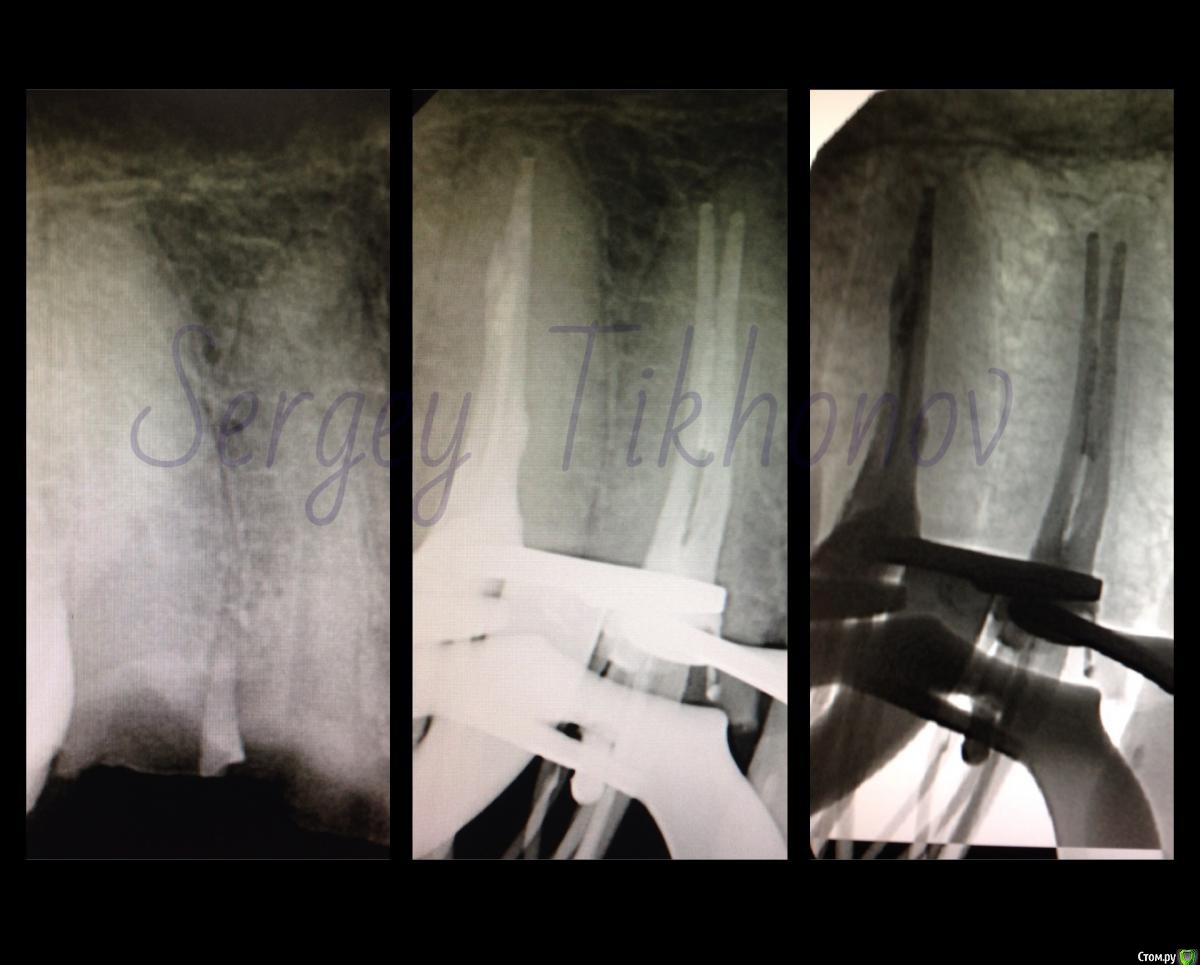

SSTi Опубликовано 21 января, 2015 Автор Поделиться Опубликовано 21 января, 2015 Легкий и приятный кейс. 46. Витальное эндо. Медиальные 35.04, дистальные 40.04. Дистальных 2. В конце инструментации ушла перегородка и они объединились в 1 протяженный щелевидный канал. Латералка. 7 Ссылка на комментарий

SSTi Опубликовано 22 января, 2015 Автор Поделиться Опубликовано 22 января, 2015 Вот нашел. Может выкладывал уже. Но вроде нет. Любимые нижние премолярки) 5 Ссылка на комментарий

SSTi Опубликовано 4 февраля, 2015 Автор Поделиться Опубликовано 4 февраля, 2015 45. Многострадальный. 1- изоляция. Преп. Извлечения штифта. 40.04-70.02. Гх-эдта-гх уз - эдта - кальций. ЦемилайтПериостотомия2- изоляция- преп- эдта- гх уз - аспирация - перекись - хг. ОбтурацияЛатералка с модификацией) 4 1 Ссылка на комментарий